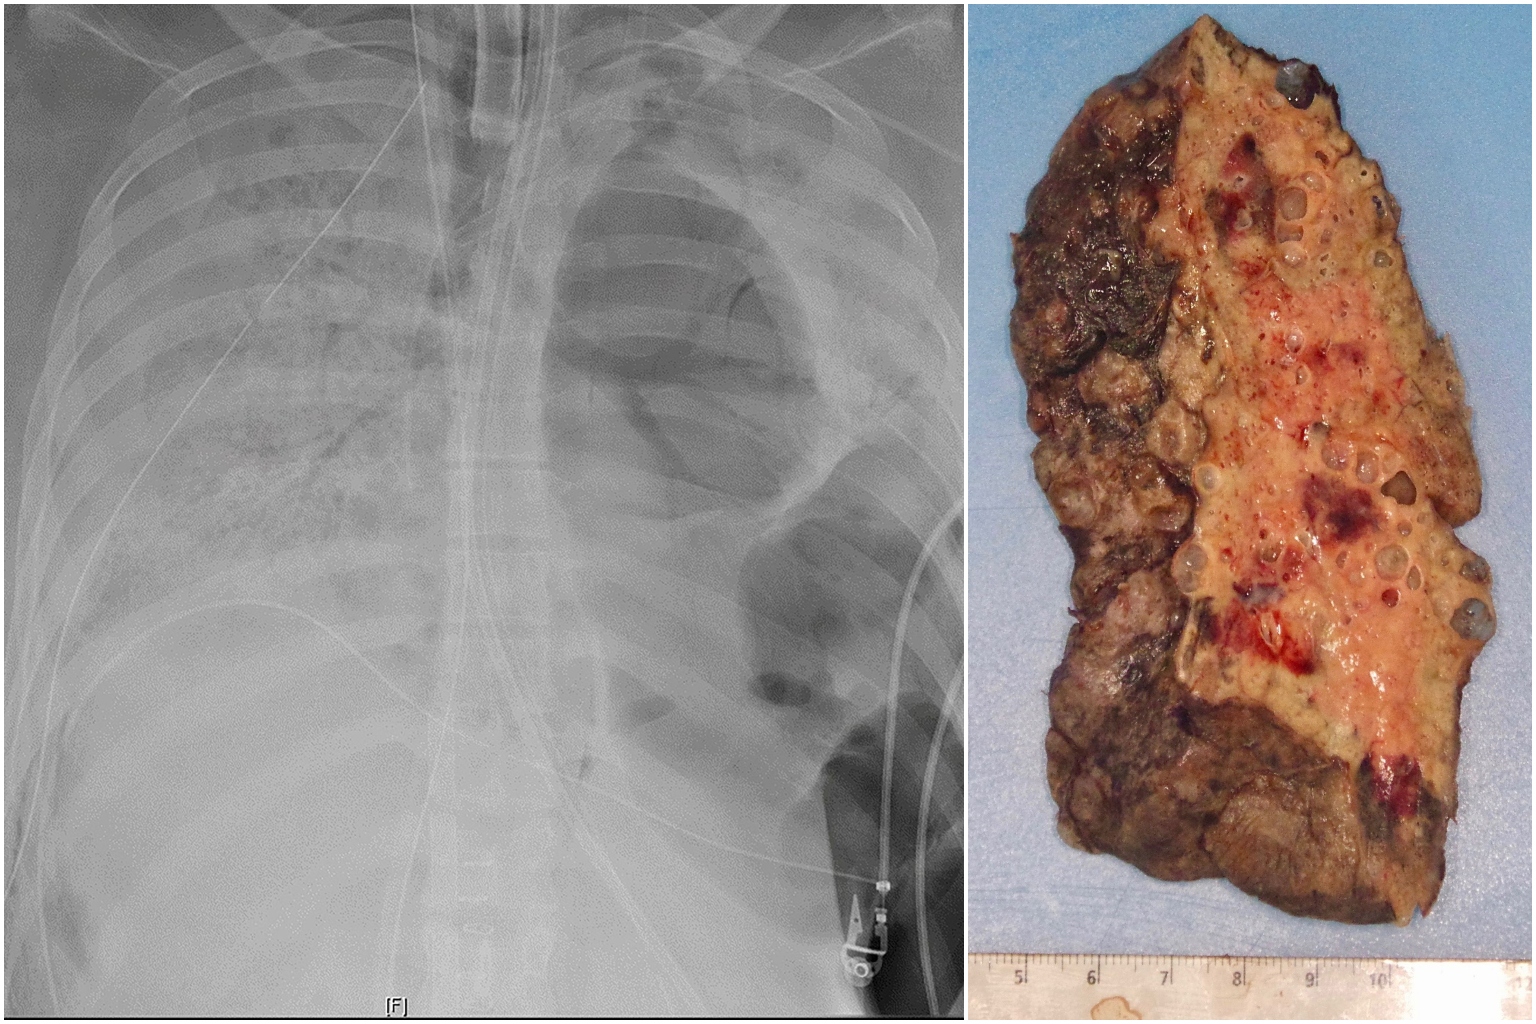

The patient's lungs had become so badly damaged that it was decided that a transplant was her only option.

By early June, her lungs had become so badly damaged that it was decided that a transplant was her only option.

"A lung transplant was her only chance for survival," said Dr Ankit Bharat, chief of thoracic surgery and surgical director of the Northwestern Medicine Lung Transplant Programme.